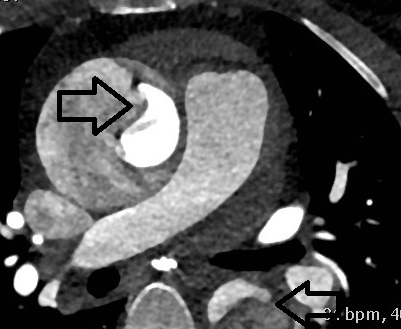

的确很奇怪,这样的描述竟然和主动脉走形如此类似。“病人的心肌酶结果出来了,都在正常范围之内,心电图给你看。”护士把心电图递给我,全导联心电图没有心肌梗死的特征性的表现。难道是夹层?!尤其是病人描述的疼痛变化,几乎就是主动脉走形的素描。摸摸患者的双侧足背动脉,搏动一致,再看看患者的CT,仔细的研读一下,我大吃一惊。患者升主动脉内血液的密度明显不均一,仔细看看降主动脉内似乎有一飘带。难道是夹层?!这一疾病起危险程度远甚于急性心肌梗死。

和患者家属仔细说说病情,目前离患者症状发作已经超过11小时了,但是心肌酶仍然不高,心电图也没有特征性的变化,基本可以排除心肌梗死了,但是有高血压病史(虽然血压似乎不是很高),这再加上疼痛发生的整个过程,还有CT表现,几乎是教科书式的主动脉夹层。然而跟根本不懂医学的家属讲病情还是需要耐心还有化复杂为简洁的能力。和家属交往久了,慢慢就会和患者家属交流了,很快家属就明白了问题所在,同意做强化CT来明确诊断。

在放射科配合下,很快CT片就摆在我们面前了,看着CT我再一次感觉“如履薄冰如临深渊”,如果就按照心肌梗死处置,那就是不可挽回的灾难性后果。

后记:急性心肌梗死、急性肺栓塞和主动脉夹层,这三种疾病构成了高危胸痛最主要的疾病谱。在急诊,在抢救室,诊断和鉴别诊断异常重要,诊断清楚了才会有正确的后续治疗,如果错误的诊断会有灾难性的后果。文中所述CT平扫不能作为诊断的依据,只能是证据的一种,在某些情况下平扫CT可以出现密度不均一,相对于密度不均一,钙化点的内移诊断价值更大。有无高血压、双上肢血压有无差别、足背动脉搏动是否一致,这些都不是诊断主动脉夹层的充分必要条件,所有这些都需要综合病史和疼痛性质来综合考虑。